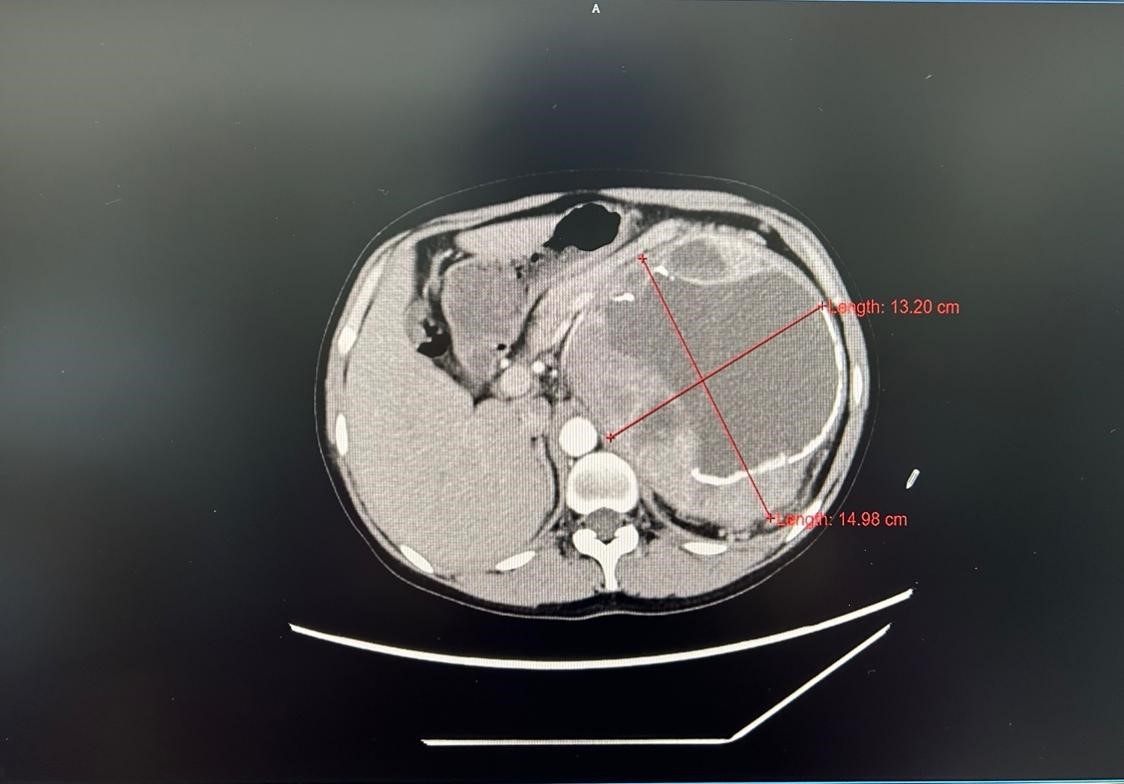

图1 术前腹部CT

患者是一位31岁青年女性,平日身体状况良好,既往无其他基础疾病。本次因“腹膜后巨大包块”入院,腹部CT提示“腹膜后肾上腺区可见一巨大囊实性包块(图1,14.8*14.2*24.4cm),疑似与下腔静脉相连,且压迫腹主动脉”,结合术前儿茶酚胺水平及患者的临床表现,考虑该肿瘤为嗜铬细胞瘤。